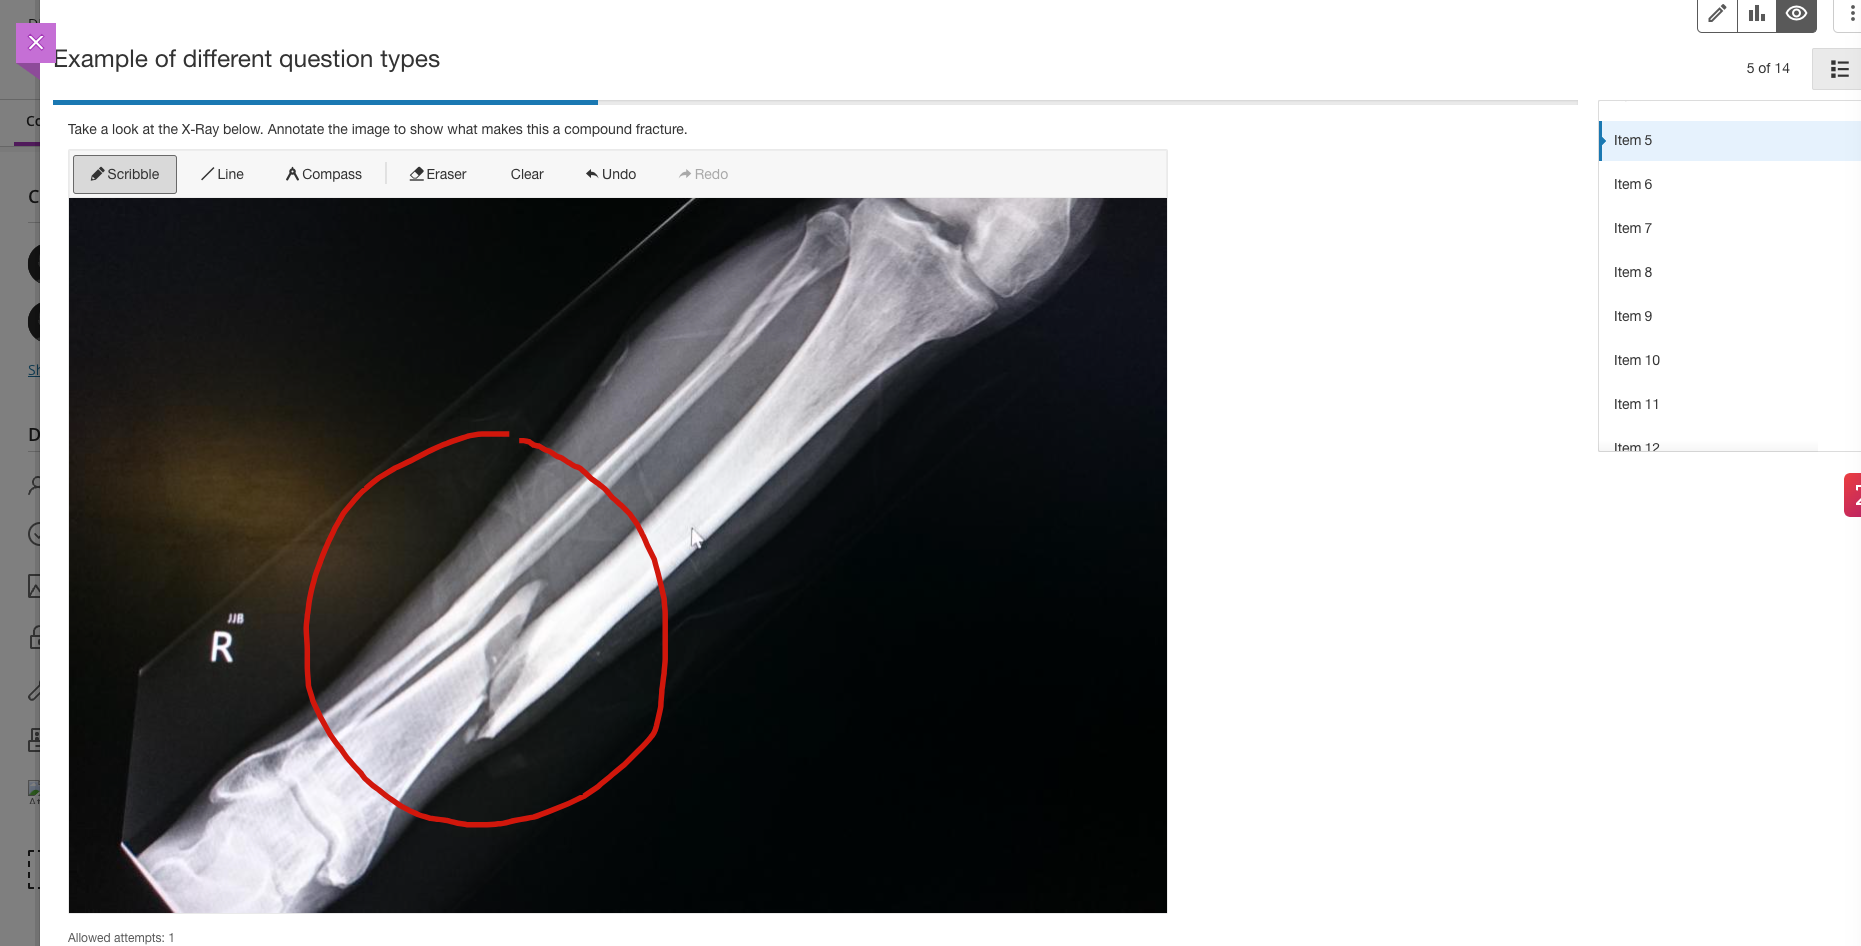

Atomic Assessments in Blackboard Learn offers a robust and flexible solution for creating, delivering, and managing various assessments. This tool allows educators to design engaging, interactive assessments with diverse question types, from simple multiple-choice to complex simulations. With advanced analytics and reporting features, instructors can gain deep insights into student performance and learning outcomes. Atomic Assessments integrates seamlessly with Blackboard Learn, providing a streamlined workflow for both instructors and students. It supports adaptive learning paths, enabling personalized feedback and tailored learning